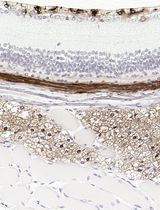

采用 Davidson 固定液和黑色素漂白法优化小鼠眼组织切片的免疫组化染色

Anne Nathalie Longakit [...] Catherine D. Van Raamsdonk

2025年11月20日 1564 阅读